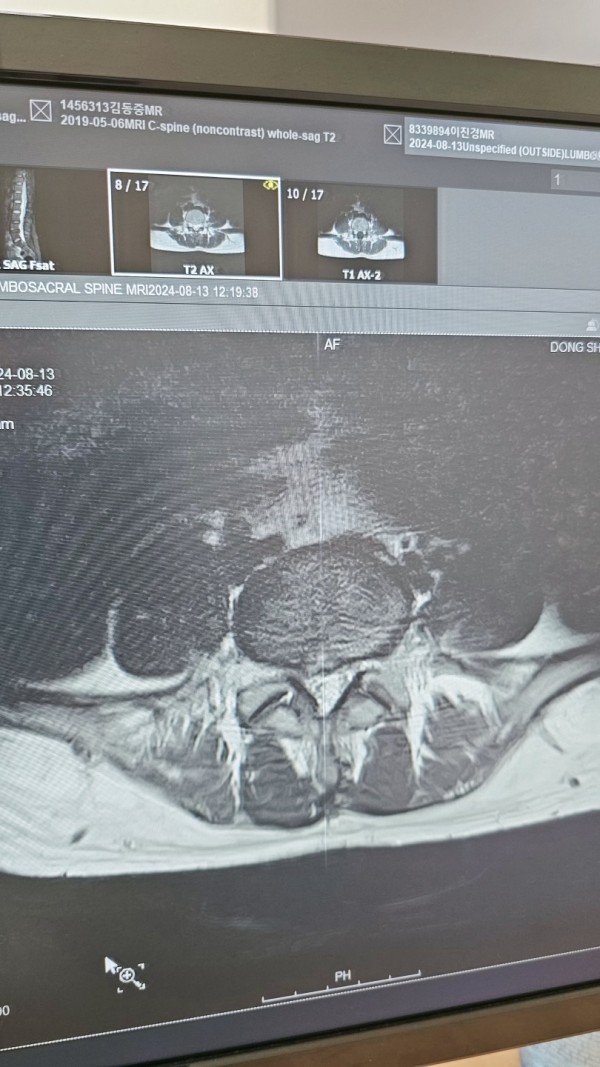

허리디스크 3.4.5번이 탈출되었다고 MRI 를 찍어서 보았습니다